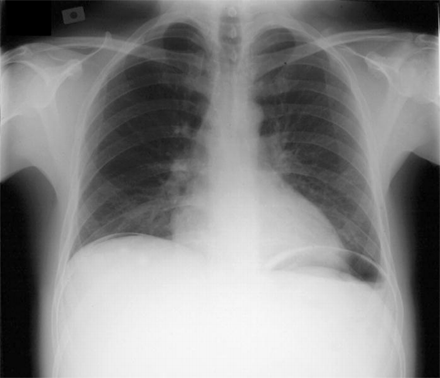

НемедицинаРентгенограмма грудной клетки, демонстрирующая наличие свободного воздуха под диафрагмой, что указывает на перфорацию кишечника.

Симптом серпа (симптом полумесяца)- радиологический признак некоторых заболеваний, выявляемый при рентгенографии и компьютерной томографии. Представляет собой серповидный участок просветления, являющийся отражением скопления газа вокруг органа или патологического образования.